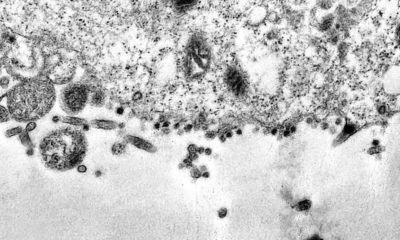

Quanto mais o novo coronavírus circula, maior a chance de ocorrer uma mutação genética e o aparecimento de novas variantes que podem prolongar e agravar a...